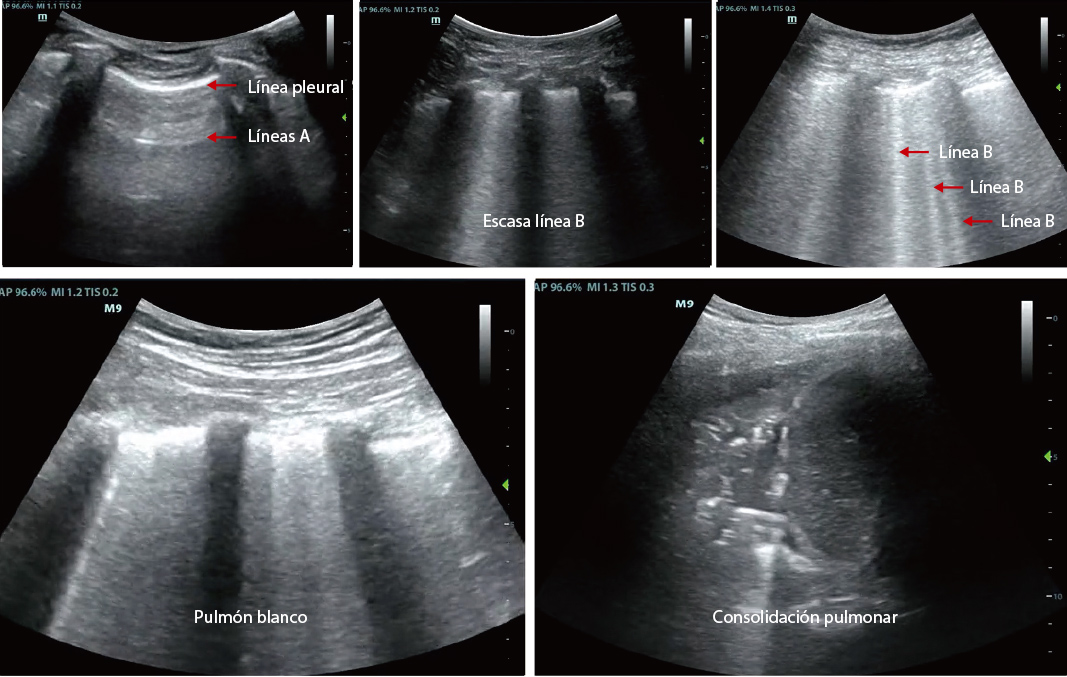

- 1. Modo de examen pulmonar profesional para observar cambios en las condiciones pulmonares